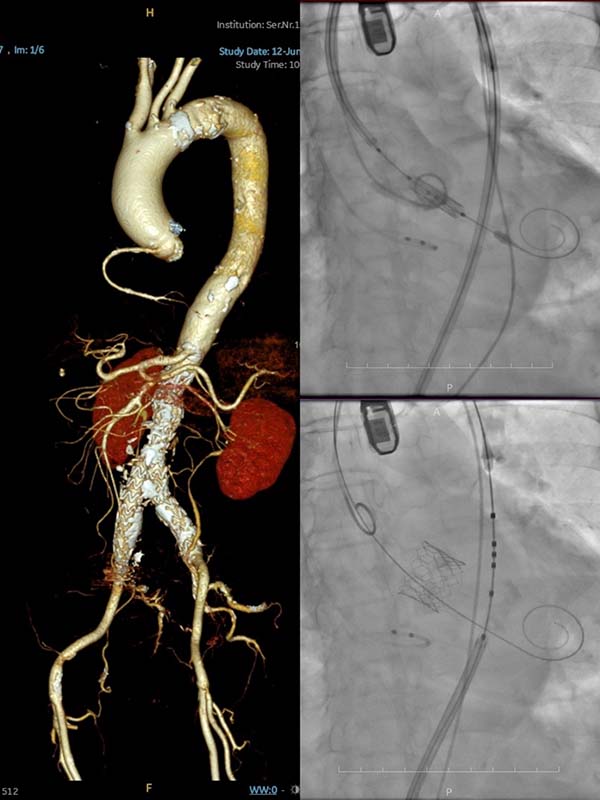

患者为81岁女性,因“活动后胸闷憋喘8年,加重半年”由外地转至省立医院。术前评估显示,患者主动脉瓣重度狭窄伴严重钙化,合并多种基础疾病,包括甲状腺癌、自身免疫性肝炎、免疫性血小板减少症、胆囊炎、高血压及冠心病等,加之半年前曾行腹主动脉支架植入术,全身血管条件差,STS外科手术风险评分高达12.1%,传统开胸手术风险极大。团队经过慎重讨论,并与患者及家属充分沟通了各种手术方案的风险与获益,最终决定采用经导管主动脉瓣置入术(TAVI)。

术前影像提示,患者主动脉瓣为三叶式、钙化严重,髂外动脉迂曲,主动脉全程广泛钙化,对输送系统的精准操作提出极高要求。王安彪主任带领主任医师訾捷、主治医师张杰术前组织了充分详细的多学科讨论。手术当天,在麻醉与围术期医学科副主任医师王洪乾、主治医师张树峰,超声医学科副主任医师宋家光及介入护理团队等多学科团队支持下,顺利为患者完成麻醉诱导。手术过程中,患者右侧股动脉入路明显钙化穿刺困难,左侧股动脉入路同样存在钙化,根据术前影像,主治医师张杰和钟京涛熟练切开左侧股动脉,游离出相对安全的穿刺入路,并成功植入操作鞘。考虑到患者腹主动脉支架植入,组装瓣膜在跨越主动脉全程中要避免损伤动脉壁,王安彪、訾捷、张杰密切配合,在影像引导下精准输送并释放瓣膜。术后即刻超声显示人工瓣膜位置理想,无明显瓣周漏,患者血流动力学显著改善。